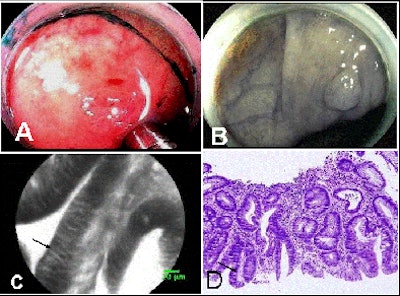

Confocal evaluation of villous adenomas revealed long, fingerlike "crypt" structures, while the adenocarcinomas in the series showed marked irregularities in the vasculatures, as well as in cell size and structure, she said.

| (A) Endoscopic view of colon with confocal microscopic probe on polyp. (B) Endoscopic view alone. (C) Confocal endomicroscopy showing single cells and fingerlike villi typical of precancerous polyps. (D) Traditional view through a microscope after polypectomy shows the same villi as in image C. All images courtesy of Dr. Anna Buchner and the Mayo Clinic, Jacksonville, FL. |